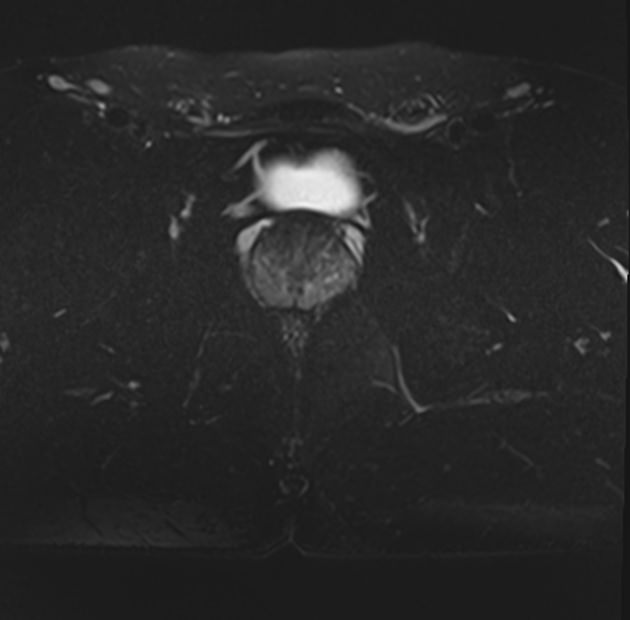

При необходимости уточнения патологических изменений, особенно при подозрении на опухолевый процесс в предстательной железе, дополнительно может применяться контрастное усиление. Это подразумевает внутривенное введение контраста, созданного на основе парамагнетика гадолиния. Контрастное вещество способно фиксироваться в патологических очагах и «подсвечивать» его под влиянием магнитного поля томографа. Методика помогает диагностировать опухоли на ранних стадиях, что повышает шансы на успешное лечение.